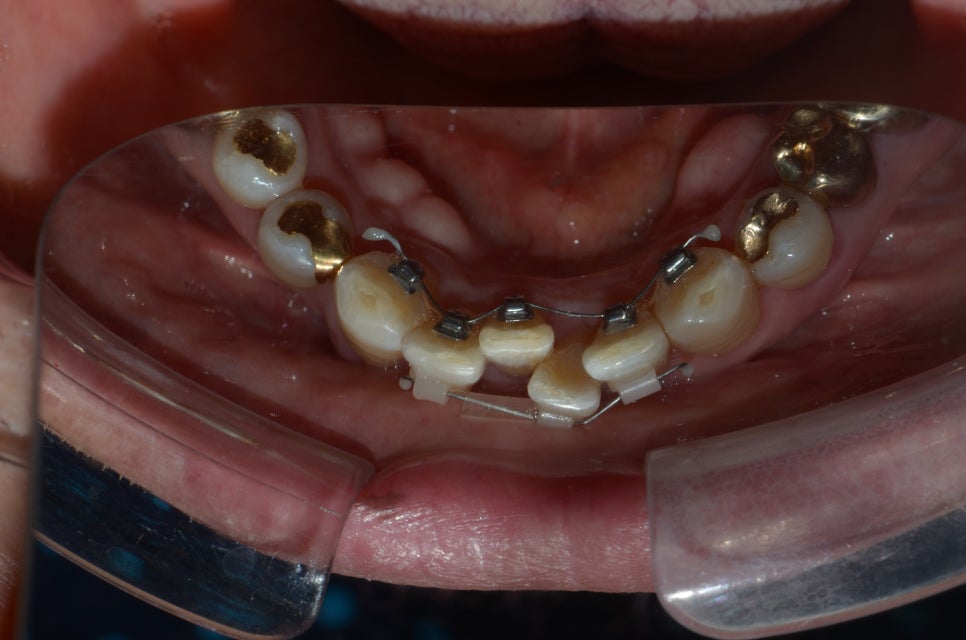

아래 앞니때문에 고민하시던 중년의 남자분 입니다.

안쪽으로 장치를 연결하고, 속도를 좀더 높이기 위해 바깥쪽에도 임시로 쌀알 크기의 장치를 몇개 부착하였습니다.

총기간은 6개월 정도 소요되었습니다.